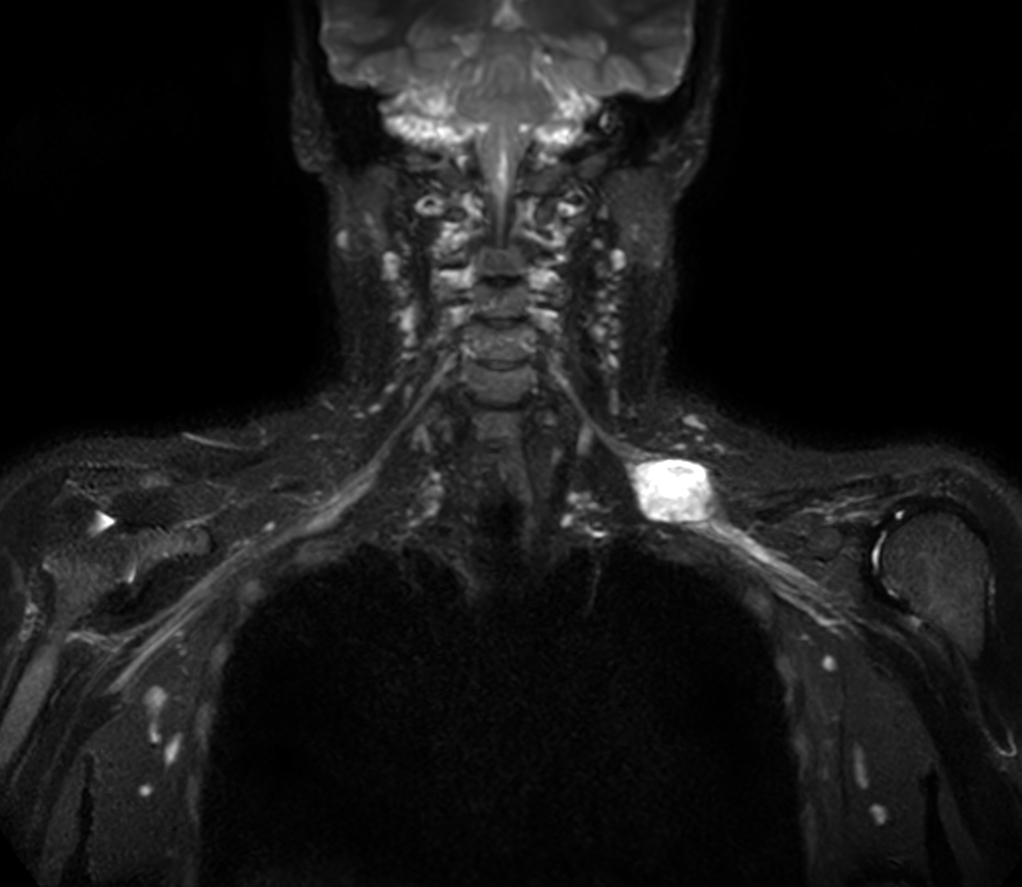

Coronal 3D STIR